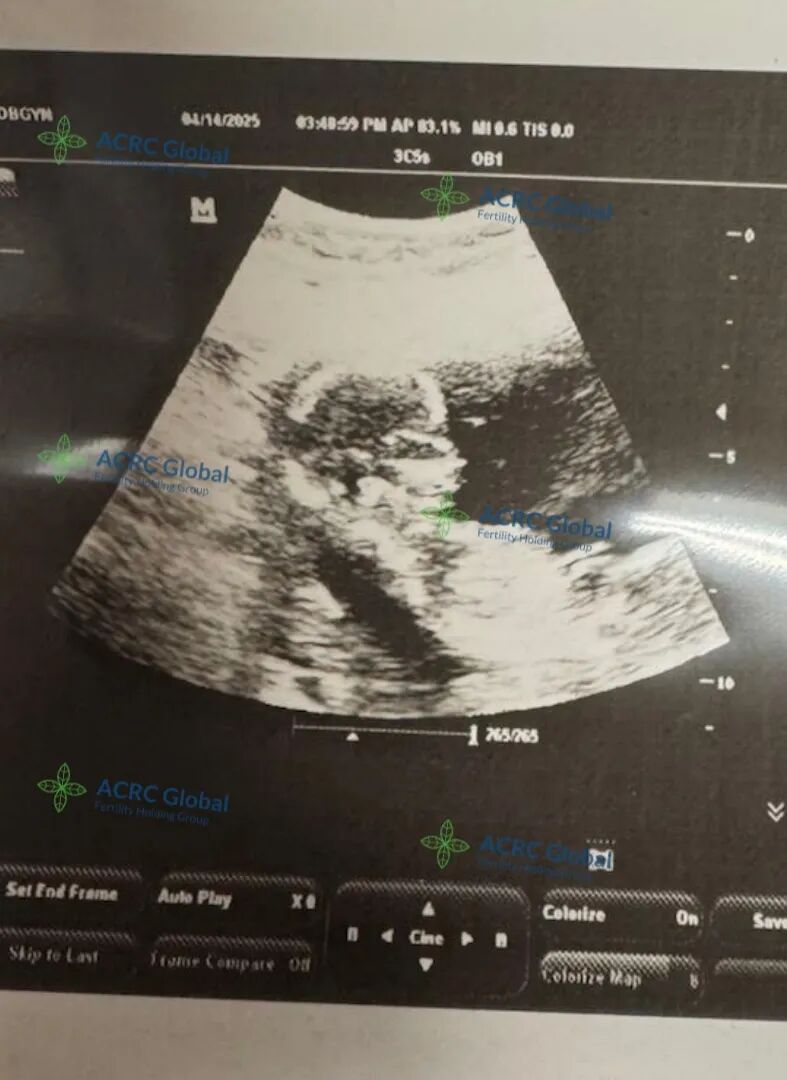

自移植以来,爱妈一直非常配合,不仅定期更新近况,还主动分享每次产检照片,让准妈妈远在国内也能放心。用药、打疫苗、日常调养,她都认真对待,事事细心,沟通顺畅,让整个孕期进展得非常顺利。大家都满怀期待,希望这个小生命能在她的温柔守护下,健康成长,顺利到来!